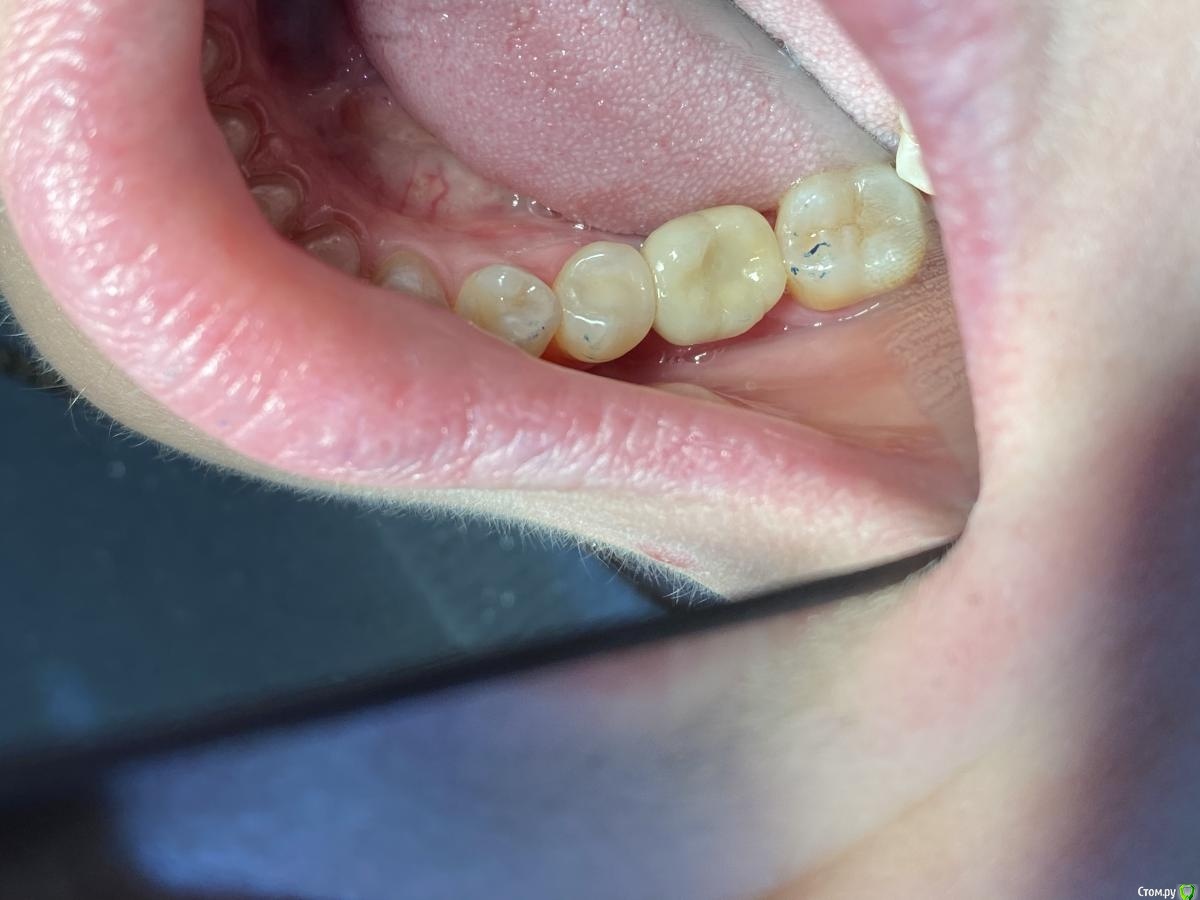

Женька Опубликовано 14 сентября, 2020 Автор Поделиться Опубликовано 14 сентября, 2020 Ну как-то вот так... Ссылка на комментарий

Irouil Опубликовано 14 сентября, 2020 Поделиться Опубликовано 14 сентября, 2020 (изменено) Не идеально, конечно, но я бы отправил уже на протезирование так на Вашем месте, прикрепленка есть, кортикалка по шейку Если включать перфекциониста, то можно пончо сделать, но нужно отслоиться через прикрепление эпителиальное, нужно и увеличение, и тунельный острый инструмент или микро хирургическое лезвие, и навык. Испортить тут можно гораздо больше, чем улучшить Основание абатмента пониже и пошире просто взять и пациента натаскать на гигиену, все ок будет Изменено 14 сентября, 2020 пользователем Irouil 1 Ссылка на комментарий

Женька Опубликовано 14 сентября, 2020 Автор Поделиться Опубликовано 14 сентября, 2020 Не идеально, конечно, но я бы отправил уже на протезирование так на Вашем месте, прикрепленка есть, кортикалка по шейку Если включать перфекциониста, то можно пончо сделать, но нужно отслоиться через прикрепление эпителиальное, нужно и увеличение, и тунельный острый инструмент или микро хирургическое лезвие, и навык. Испортить тут можно гораздо больше, чем улучшить Основание абатмента пониже и пошире просто взять и пациента натаскать на гигиену, все ок будетЯ придерживаюсь этого же мнения...Я скорее испорчу то, что получилось. Эти фото с формирователем 4.5, 3 месяца ходили с 4.0На этапе прикручивания 4.5, пациентка отметила легкое жжение... на фдм метрогил был...вот думаю, то ли это на метрогил такая реакция, то ли я что-то задавил? Планировали на тибейзе geo делать... там варианта пошире насколько я знаю нет. 4.5 и размеры по вертикали cut и длинные З.Ы. Вчера у Ильгама Ирековича на курсе впервые познакомился с галилеями от экзама... всего 2.8, быстро привыкли глаза (учитывая, что они не индивидуально под меня были)... это просто какой-то другой мир. Ссылка на комментарий